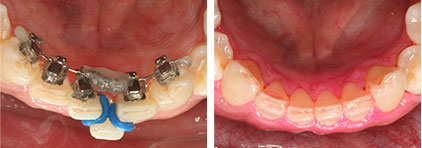

舌側矯正

顧名思義就是將矯正器由頰側的牙面改黏在舌側或顎側,矯正期間不易被發覺,屬於隱形矯正的一種,效果又比牙套式的隱形矯正有效率,對於不想被人發現在做矯正或是對外型非常要求的人非常合適。